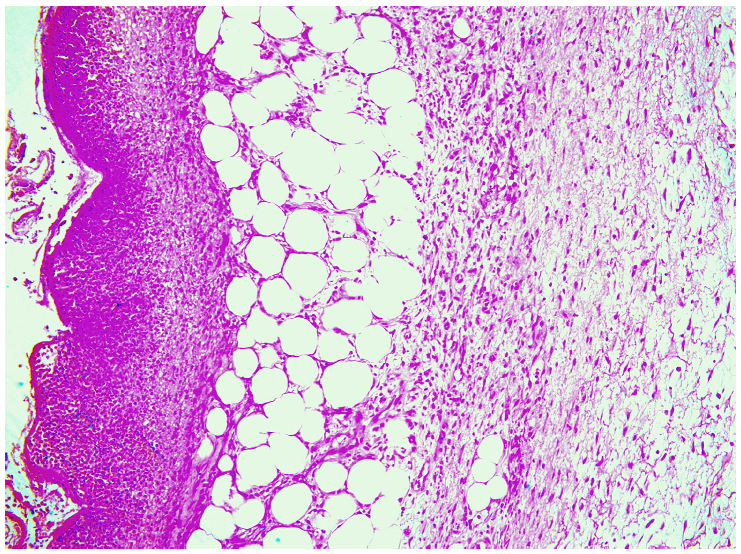

—fibrin clot,

—granulation tissue,

—fibrotic tissue,

—adipose tissue.